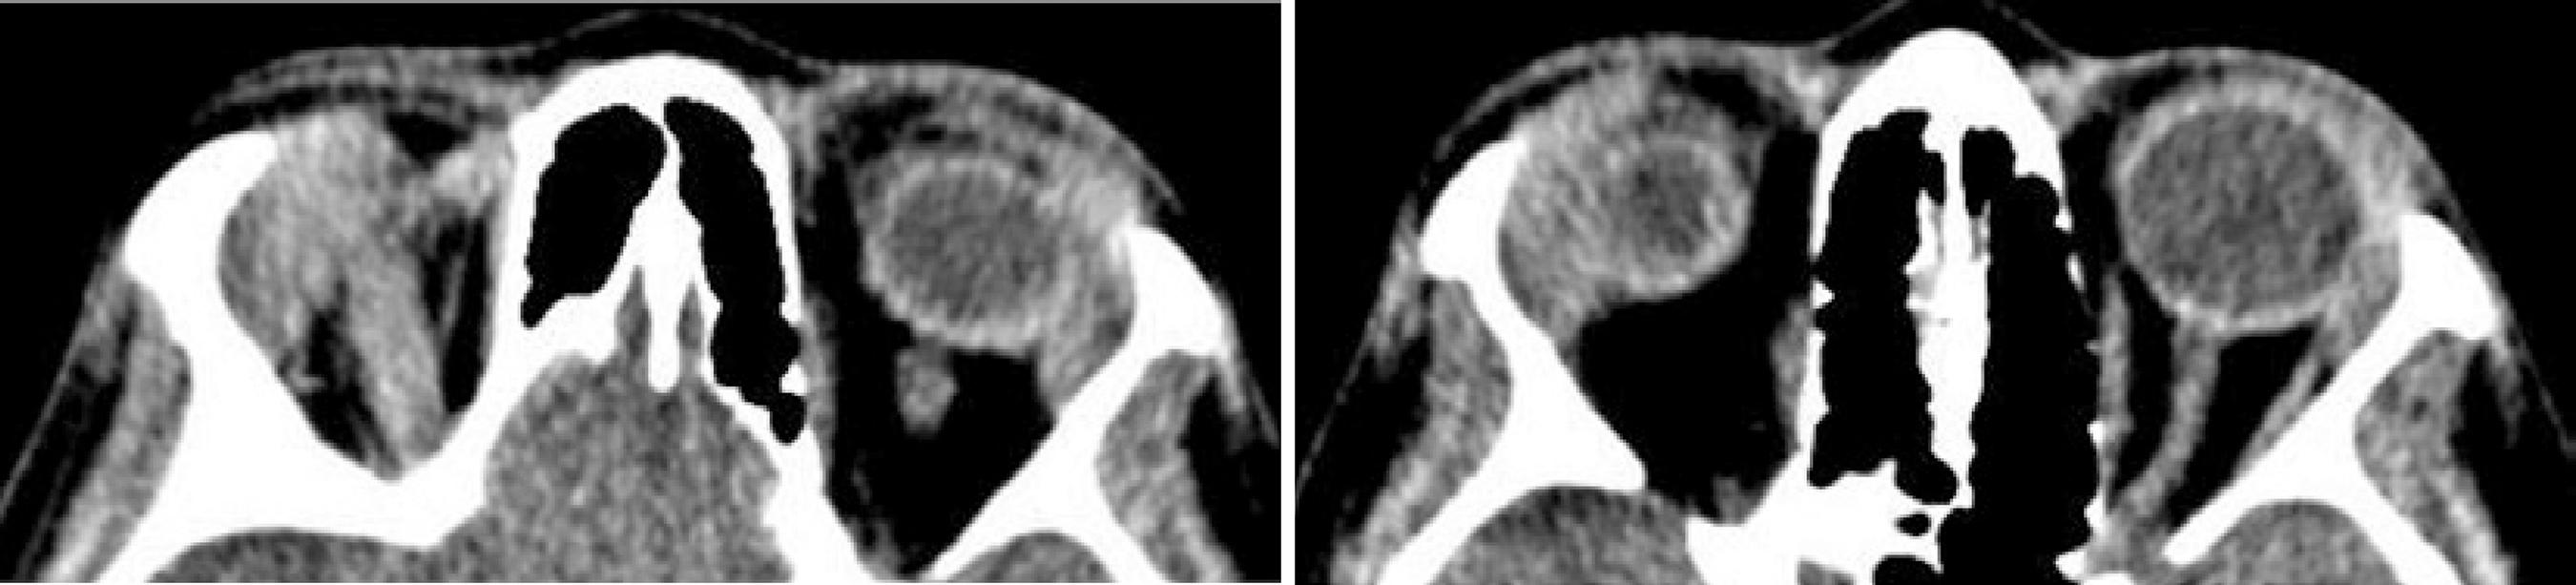

Empirical treatment for ocular toxoplasmosis was started (oral sulfamethoxazole + trimethoprim 800/160 mg 1 pill twice a day and oral prednisone 1 mg/kg/day in regression 20 mg every 3 days) as well as topical treatment with prednisolone acetate 1% and tropicamide 1% drops in OU. After 3 weeks, the patient returned with improvement of systemic symptoms and bipalpebral edema but with worsening of retinal vasculitis in OU. Computed tomography (CT) of the orbit showed a bilateral increase in lacrimal glands (Figure 3), and chest X-ray radiography showed increased hilar lymph nodes and some pulmonary infiltrates, signs that were consistent with the diagnosis of pulmonary sarcoidosis stage II. The diagnosis of presumed ocular sarcoidosis was made. Antibiotics were discontinued and slowly regressive oral prednisone 1 mg kg-1day-1 and methotrexate were started. The patient showed clinical improvement, and after 1 year of follow-up, she presented without systemic or ocular complaints, with a BCVA of 20/20 in OU. Ocular examinations subsequently showed that she continued to exhibit sporadic small areas of vasculitis in OU, without other complications.